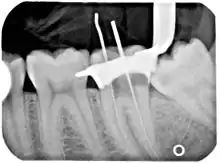

Another common complication of root canal therapy is when the entire length of the root canal is not completely cleaned out and filled (obturated) with root canal filling material (usually gutta percha). On the other hand, the root canal filling material may be extruded from the apex leading to other complications.[47] The X-ray in the right margin shows two adjacent teeth that had received bad root canal therapy. The root canal filling material (3, 4 and 10) does not extend to the end of the tooth roots (5, 6 and 11). The dark circles at the bottom of the tooth roots (7 and 8) indicated infection in the surrounding bone. Recommended treatment is either to redo the root canal therapy if possible, or extract the tooth and place dental implants.